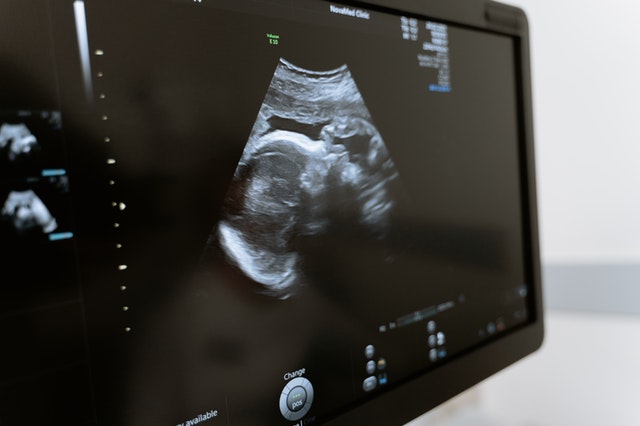

Sonogram and ultrasound are terms that many people use interchangeably. An ultrasound is a device that uses sound waves to create an image. Simply by gliding a device over your body, a trained professional can reveal an image of your baby. Those images are known as a sonogram, and they are the baby’s first images.

Sonograms have been around for a long time but were first used by obstetricians in the 1960s. By the 1970s, the practice of using an ultrasound device during pregnancy to monitor the health of the unborn child started to become standard. As technology improved, the quality of the images became more precise and detailed. For many years, sonograms provided a 2D image, but advancements in technology allow professionals to create 3D and even 4D images that show greater detail.

The third scan is the basic anatomy scan, and this is the scan that parents generally look forward to and what most people usually associate with the idea of having an ultrasound. The third sonogram is a transabdominal ultrasound, and it is performed at five months or 20 weeks, and this is a complete look at the fetus. The objective is to confirm that the baby is developing at the proper and expected rate and all of the organs are present and in the correct locations.

During the basic anatomy scan, the technician applies gel to the patient’s midsection and glides a handheld transducer device over the stomach area. The gel helps the soundwaves travel through the skin, and the transducer sends the images to equipment that shows the images on a display. This scan usually takes at least 45 minutes, but it can take a few hours if the little one is not cooperating.

3D and 4D Scans